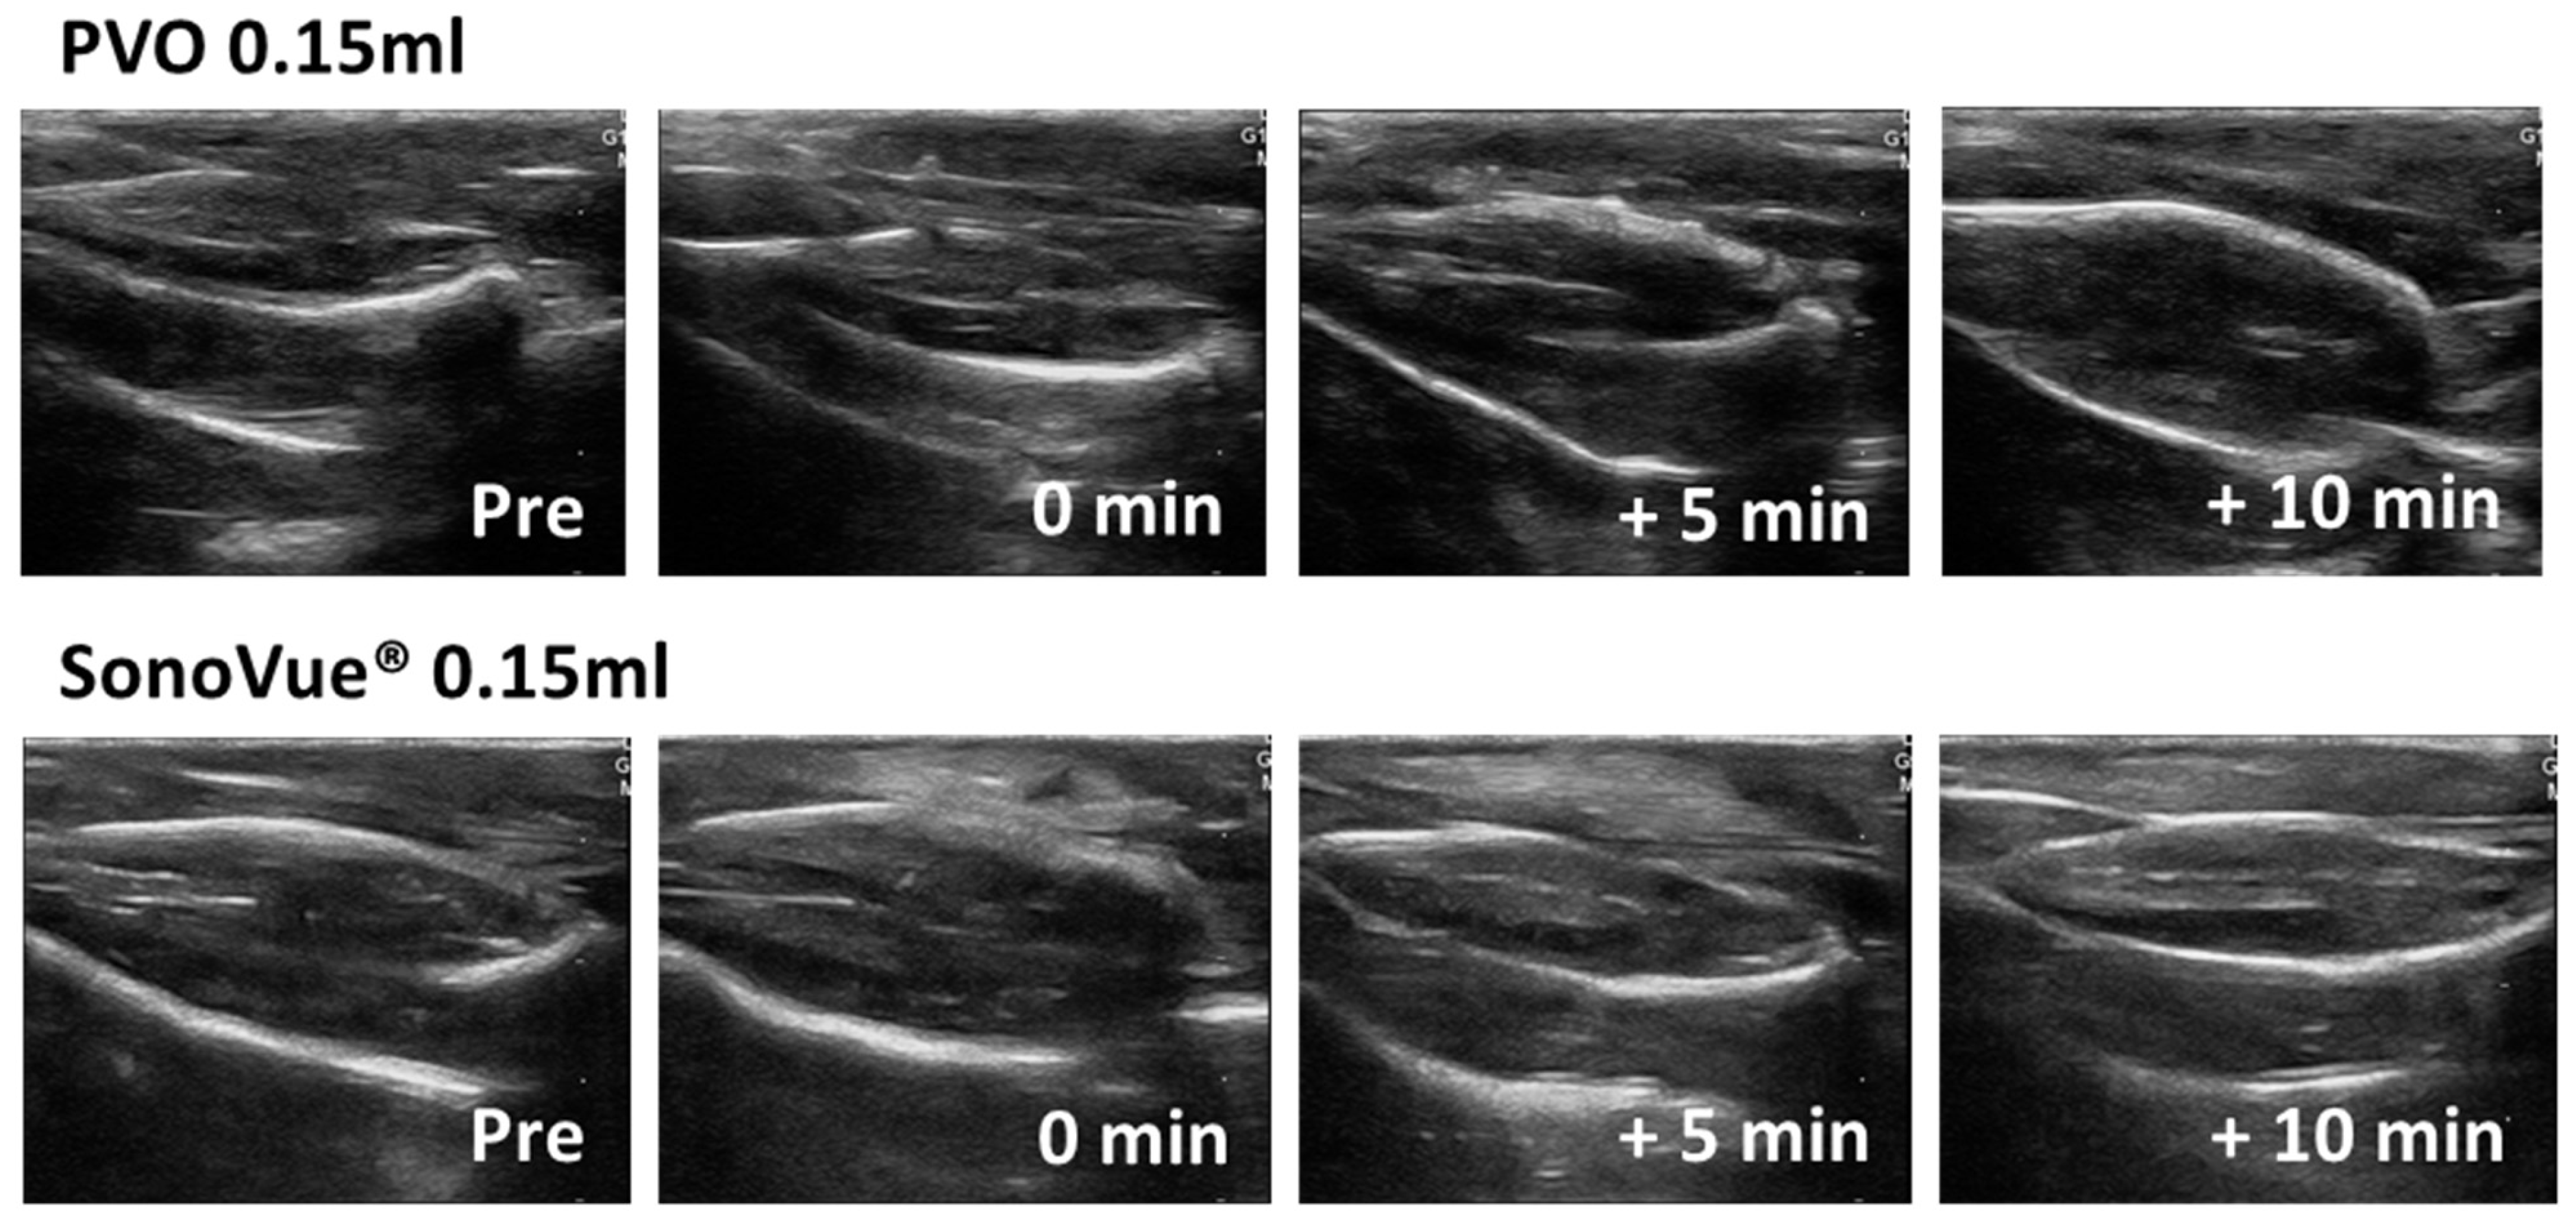

From www.mdpi.com

Diagnostics Free FullText Comparison of Ultrasound Contrast Ultrasound Contrast Contraindications This has been accompanied by the removal and/or reductions of prior contraindications to use and the provision of new clinical data to support use in pediatrics as well as non approved. Contrast echocardiography has evolved into a. Despite significant advances in ultrasound transducer design and signal processing technology, echocardiographic. At present, the only remaining contraindications to ultrasound contrast agent administration. Ultrasound Contrast Contraindications.